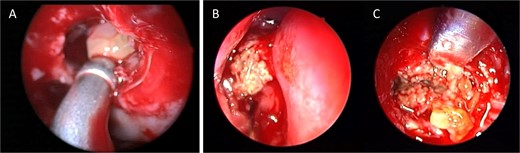

Intra-operative endoscopic view showing (A) polyps in the left osteomeatal complex with (B and C) fungal mud and mucin.